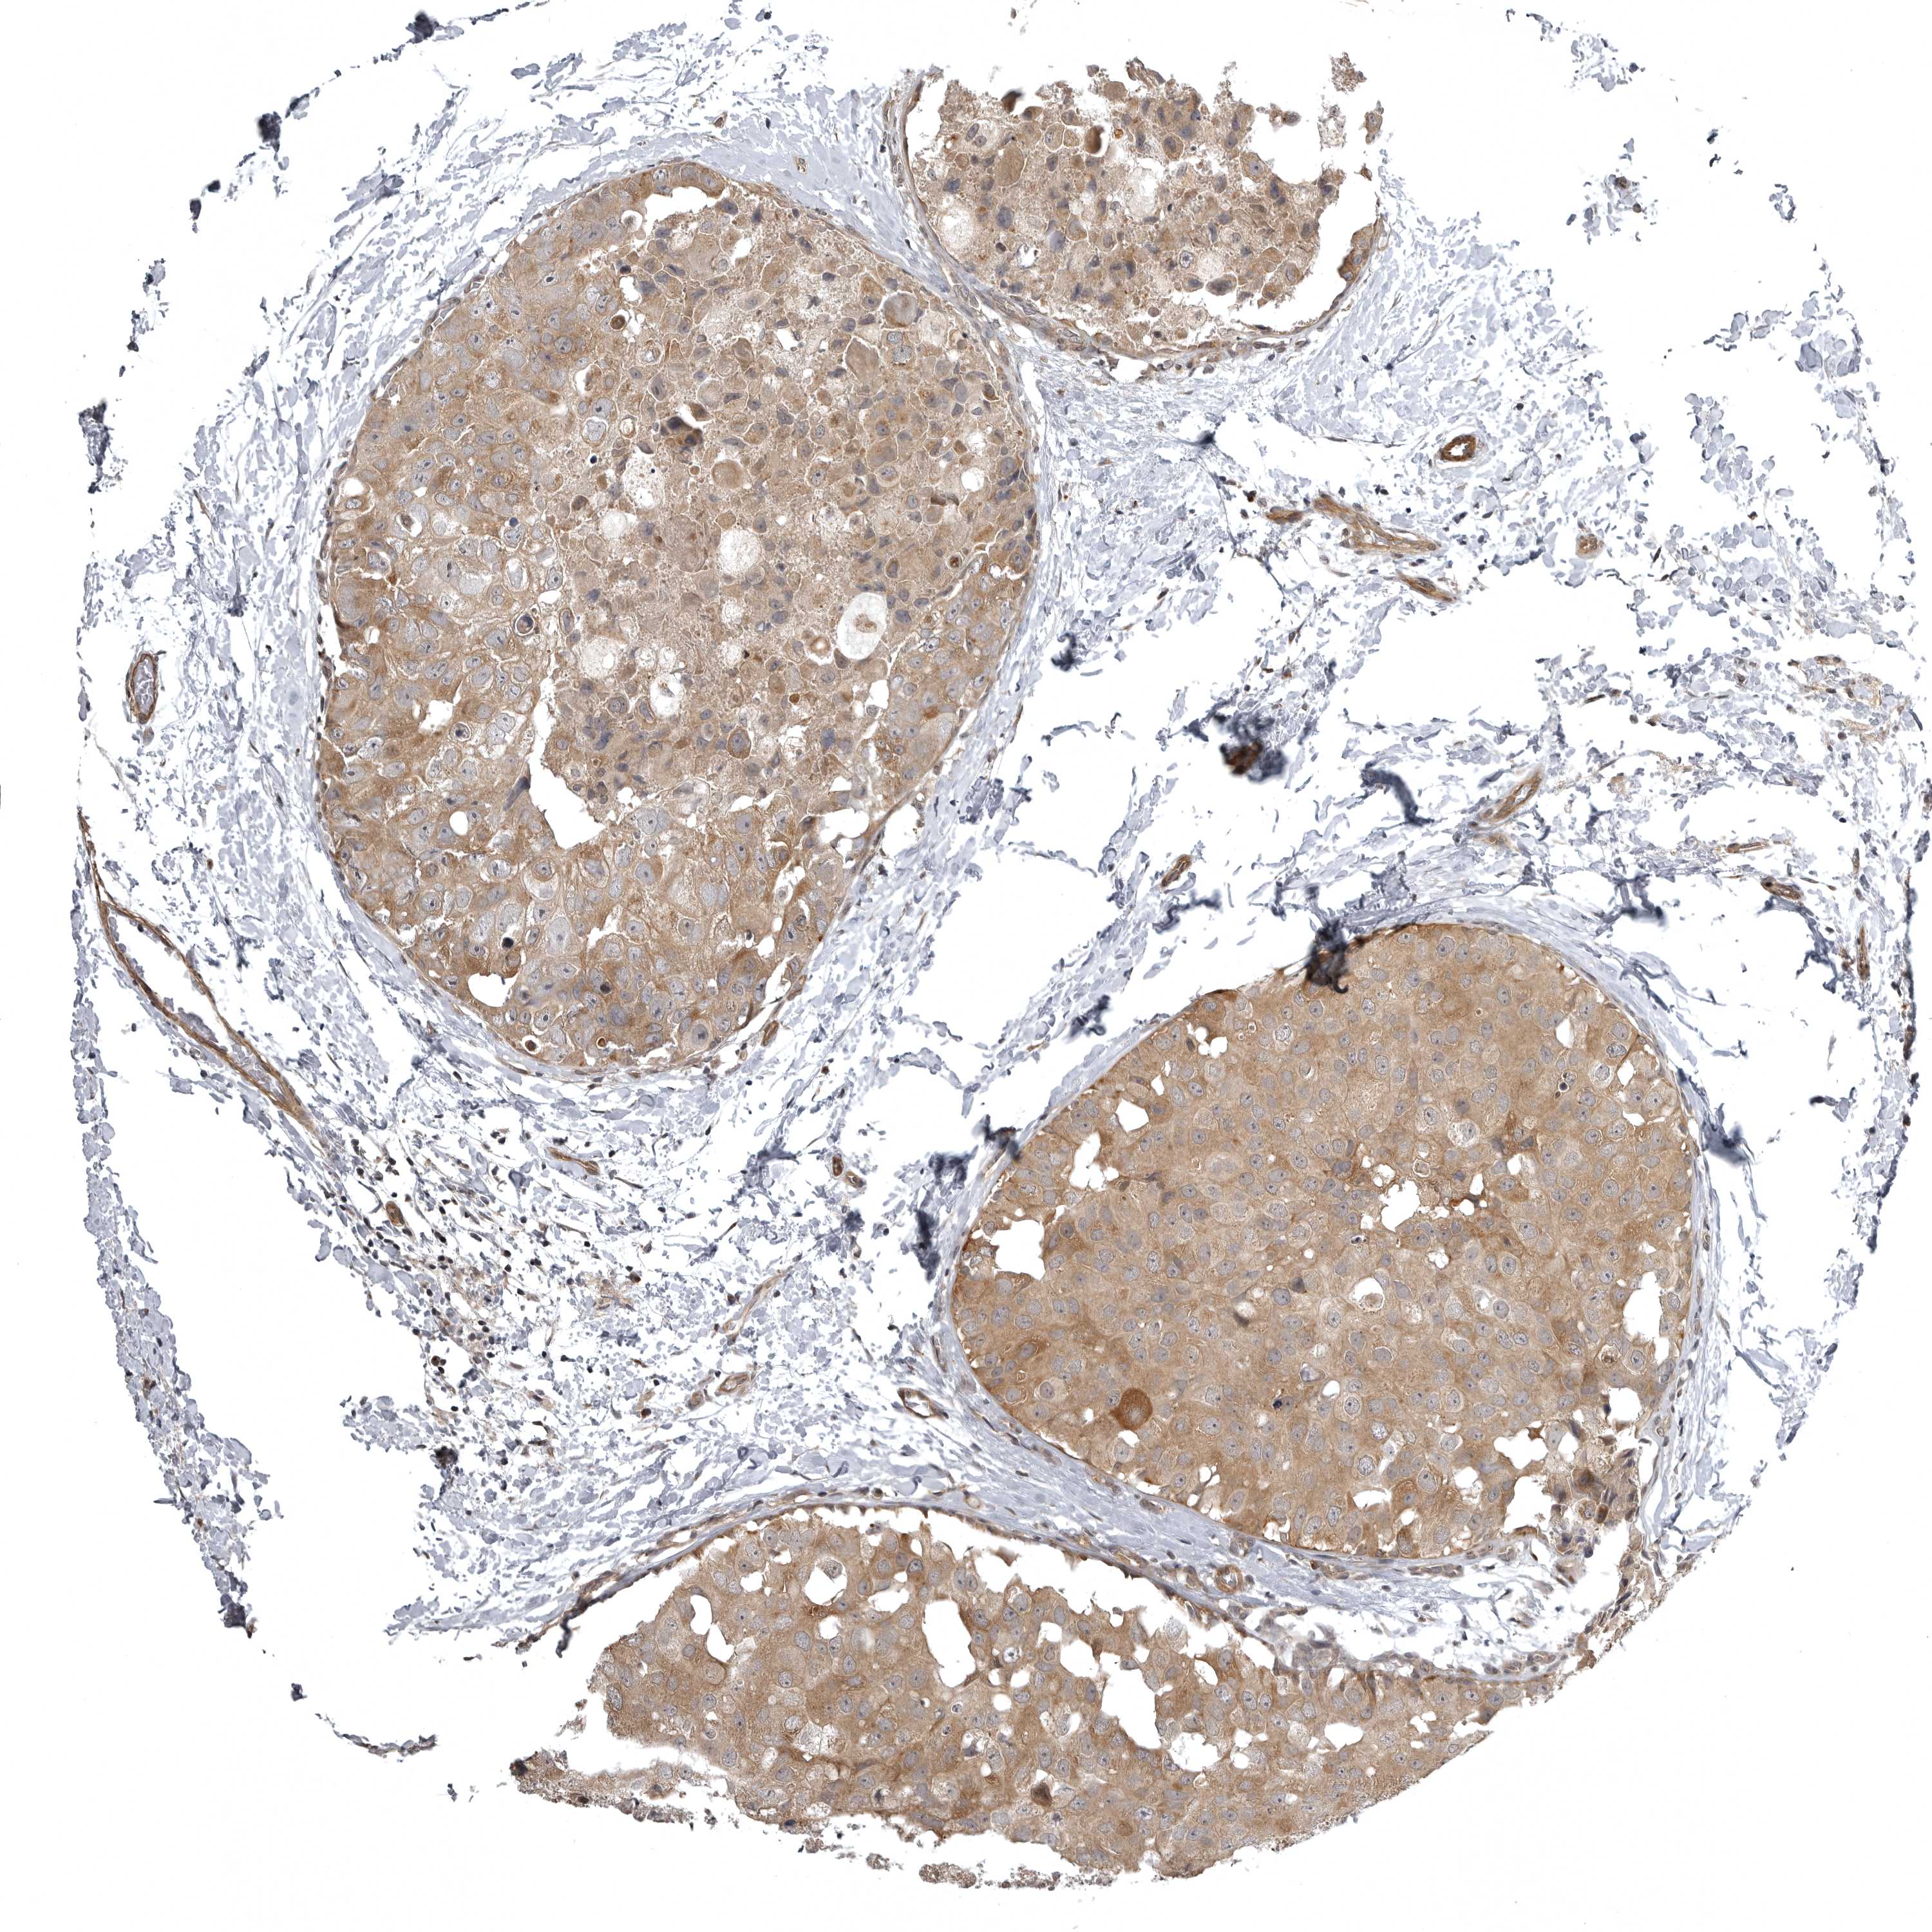

CANCER BREAST CANCER Show tissue menu

BRCA TCGA BRCA VALIDATION PROTEIN EXPRESSION